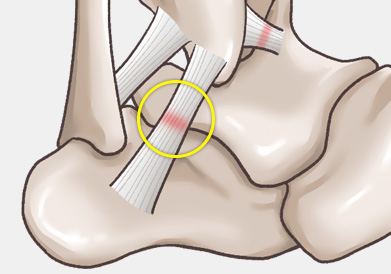

발목 인대 파열은 발목 관절을 지지하는 인대가 외부 충격이나 과도한 움직임으로 인해 늘어나거나 찢어지는 손상을 말합니다.

주로 다음 그림처럼 내반(inversion)에 의해 바깥쪽 인대가 파열되는 경우가 흔하며, 그 중에서도 전거비인대 및 종비인대의 손상 여부가 수술을 결정하는 데 가장 중요합니다.